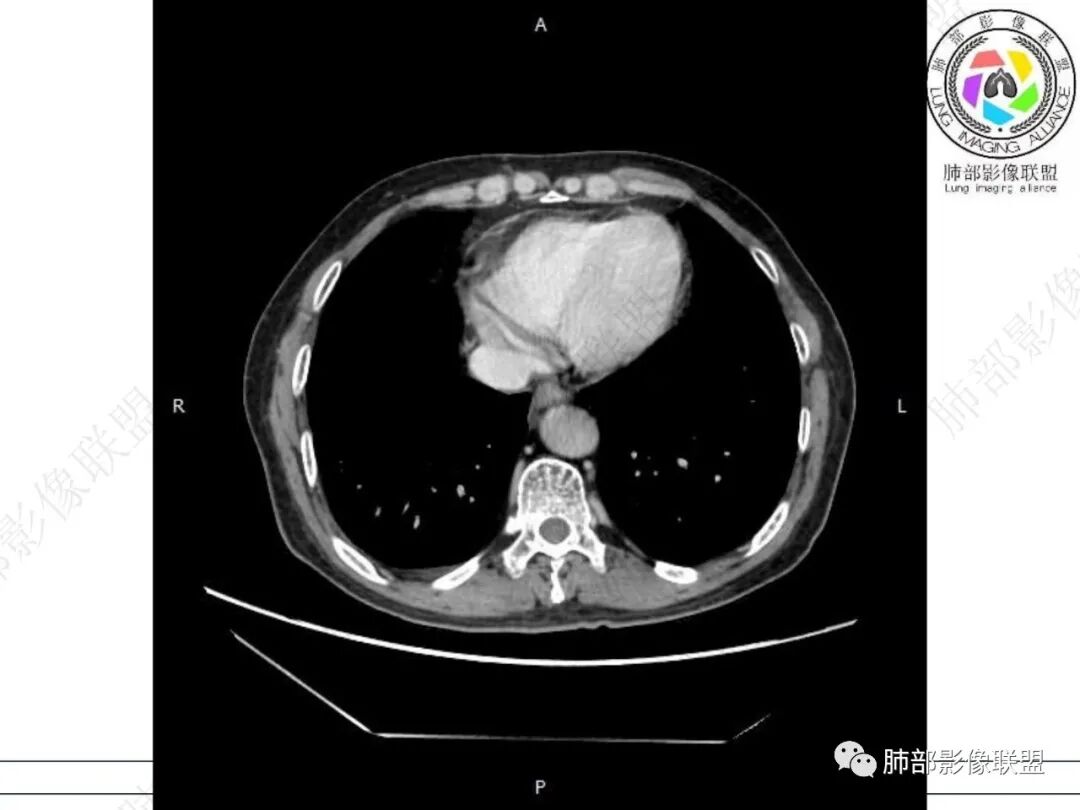

气管隆突下团片影,其内积气,与食道分界不清,食道壁增厚,管腔狭窄,右下肺实变影,支气管壁增厚,考虑食管支气管瘘并右下肺感染,食道肿瘤病变不除外

支持食管支气管瘘(考虑食管癌)伴后纵隔及右肺感染,食管管壁明显增厚,管腔狭窄,相邻右侧后纵隔内软组织内可见气体影,与食管分界不清,右肺有实变及不张。

右肺下叶背段条片状实变影,内可见支气管走行,支气管有狭窄有扩张,周围可见磨玻璃影,隆突下团片影,内密度不均可见气体影,与周围结构界限不清。食管下段壁增厚,管腔狭窄,右肺下叶慢性炎、肺不张,考虑食道肿瘤所致气管食管瘘。

老年男性,慢性病程,右肺下叶斑片影、斑点影、实变影,支气管轻度扩张,病灶整体稍收缩;食道壁增厚、肿胀、模糊,气管隆突及右后纵隔旁见软组织块影,其内见气泡影,均匀强化,符合食道支气管瘘伴周围炎症,右下肺炎症

右肺下叶沿肺叶肺段分布斑片、条片状影,以下叶背段为显,边缘模糊,内可见支气管走行,局部支气管管壁增厚,右侧胸腔少量积液。纵隔隆突下可见不均匀软组织密度影,与周围结构分界不清,内见气体密度影,与食管及相邻右肺支气管之间未显示通道。邻近食管下段壁明显不规则增厚,增强后食管管壁明显不均匀强化,可见线样强化的连续完整粘膜影。

右肺下叶片影,气道相关,符合感染性病变。纵隔隆突下软组织密度影,异常气体影,长病程,起病缓慢,提示存在气管或食管瘘。食管镜未见明显新生物形成,临床未提供进食或饮水呛咳临床表现,综合分析应该考虑支气管瘘的形成。